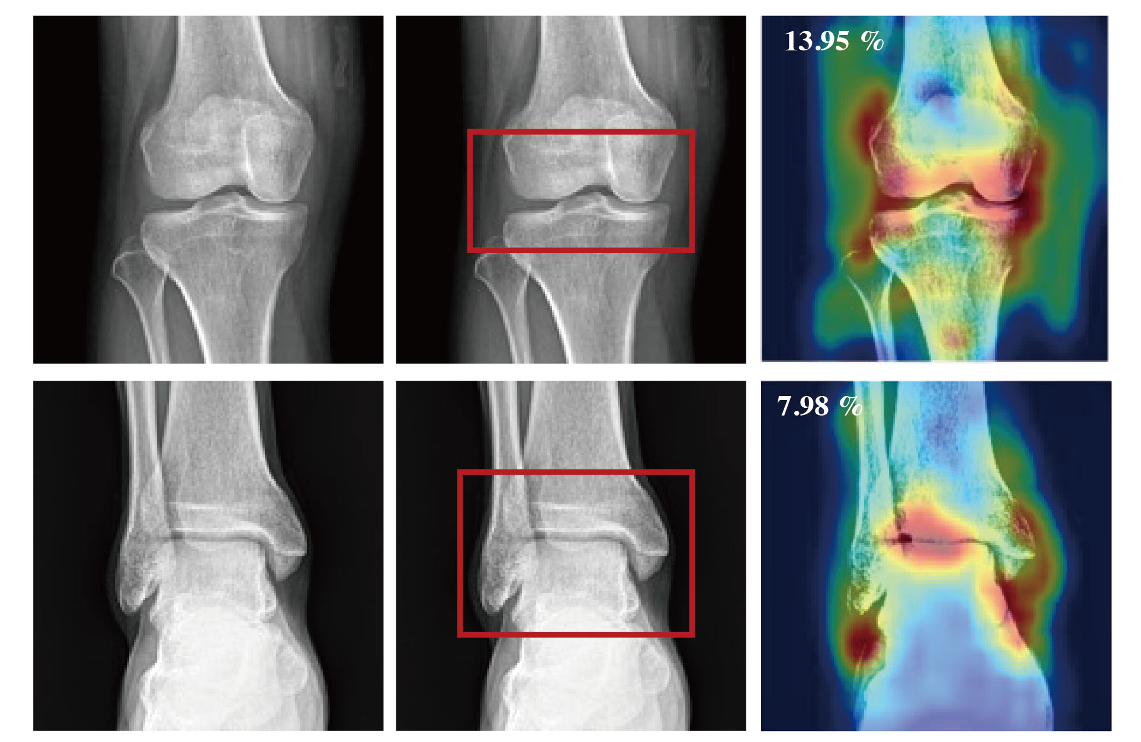

Bong Kyung Jang*, Shiwon Kim*, Jae Yong Yu, JaeSeong Hong, Hee Woo Cho, Hong Seon Lee, Jiwoo Park, Jeesoo Woo, Young Han Lee†, Yu Rang Park†

La Radiologia Medica (IF 2024: 9.7)

[TL;DR] [Paper] [Slides] [Code]

Developed and validated a continual learning framework for arthropathy grade classification scalable across multiple joints, using hierarchically labeled radiographs of the knee, elbow, ankle, shoulder, and hip from three tertiary hospitals.

La Radiologia Medica(IF 2024: 9.7)